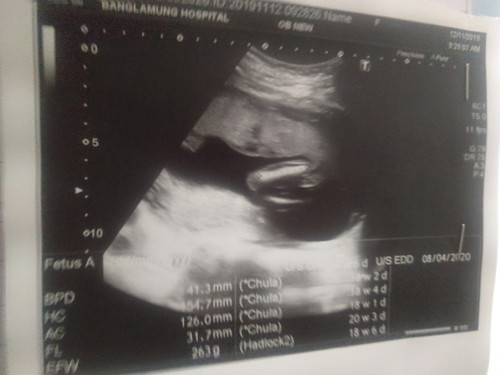

แบบนี้ผู้หญิงหรือผู้ชายค่ะ

ไม่เห็นจู๋เรย น่าจะผู้หญิงค่ะ หมอบอกแม่หรือยังคะ

น่าจะ ญ นะค่ะ ไม่เห็นจู๋เลย

หมอซาวด์ตอนกี่วีคคะ

18วีคค่ะ

น่าจะผู้หญิงนะคะ

หมอบอกผู้หญิงค่ะ